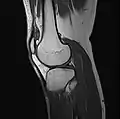

Imaging

MRI

Both anterior cruciate ligament (ACL) and posterior cruciate ligaments (PCL) are hypointense on both T1 and T2 weighted images of MRI. However, some high signal striations are often seen at the distal part of the ACL, making ACL higher intensity than PCL on MRI scans.[17]

- Knee MRI (PD TSE FS sagittal)